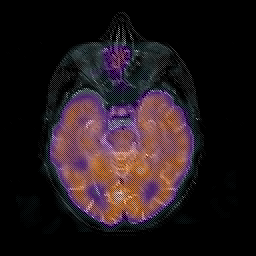

Normal aging, overlay -- Slice #20

[Home][Help][Clinical] Slice 20